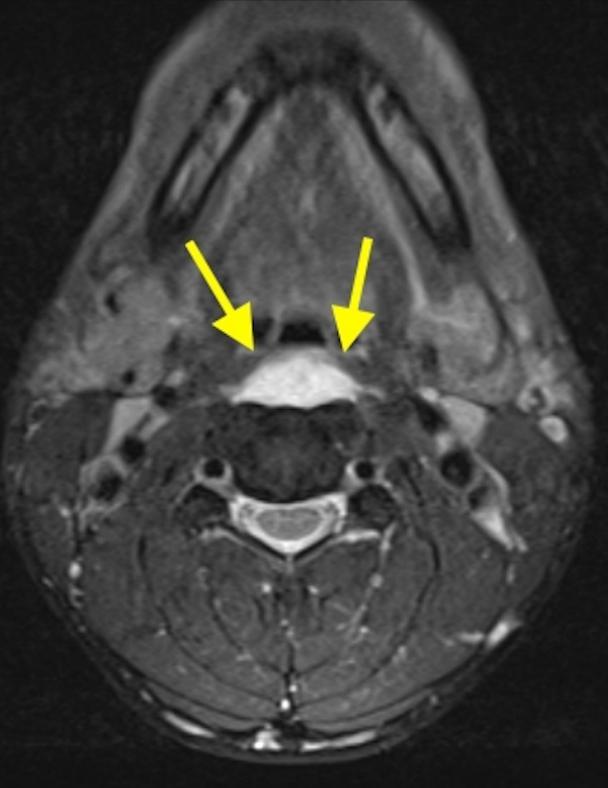

CT的高分辨率能够明确肌腱内的钙化,能够明确是钙化而不是其他骨骼来源的高密度影。 钙化一般位于寰椎前弓的下方和枢椎齿状突的前方,少部分可位于下颈椎前侧 。CT有助于明确椎体前积液的存在和排除其他病理表现,如骨折或脓肿。MRI对诊断不是必须,但有时可帮助确定软组织异常,排除咽后脓肿,脊椎炎或肿瘤。 MRI检查T2加权在椎前可见局限性的裂隙样区域,大多位于C1-4水平,呈高信号改变,这反应是由于炎症引起的积液 。T2加权、脂肪抑制序列和T1加权对鉴别积液和脂肪组织、含脂肪的骨髓以及咽后感染、脊椎炎有重要作用。MRI检查在钙化检查方面存在不足,T2加权呈低信号。

36岁女性,急性颈痛、吞咽困难伴颈部僵硬,MRI示C1-2前部颈长肌增厚呈低信号,提示钙化(长箭头)和C1-4椎前积液(无线箭头),经类固醇和止痛药治疗8天后症状消失,复查MRI提示上述表现消失。(PMID: 18765656)

C1-2前侧低信号(无线箭头)和C1-5椎前水肿(长箭头)

(PMID: 19567634)